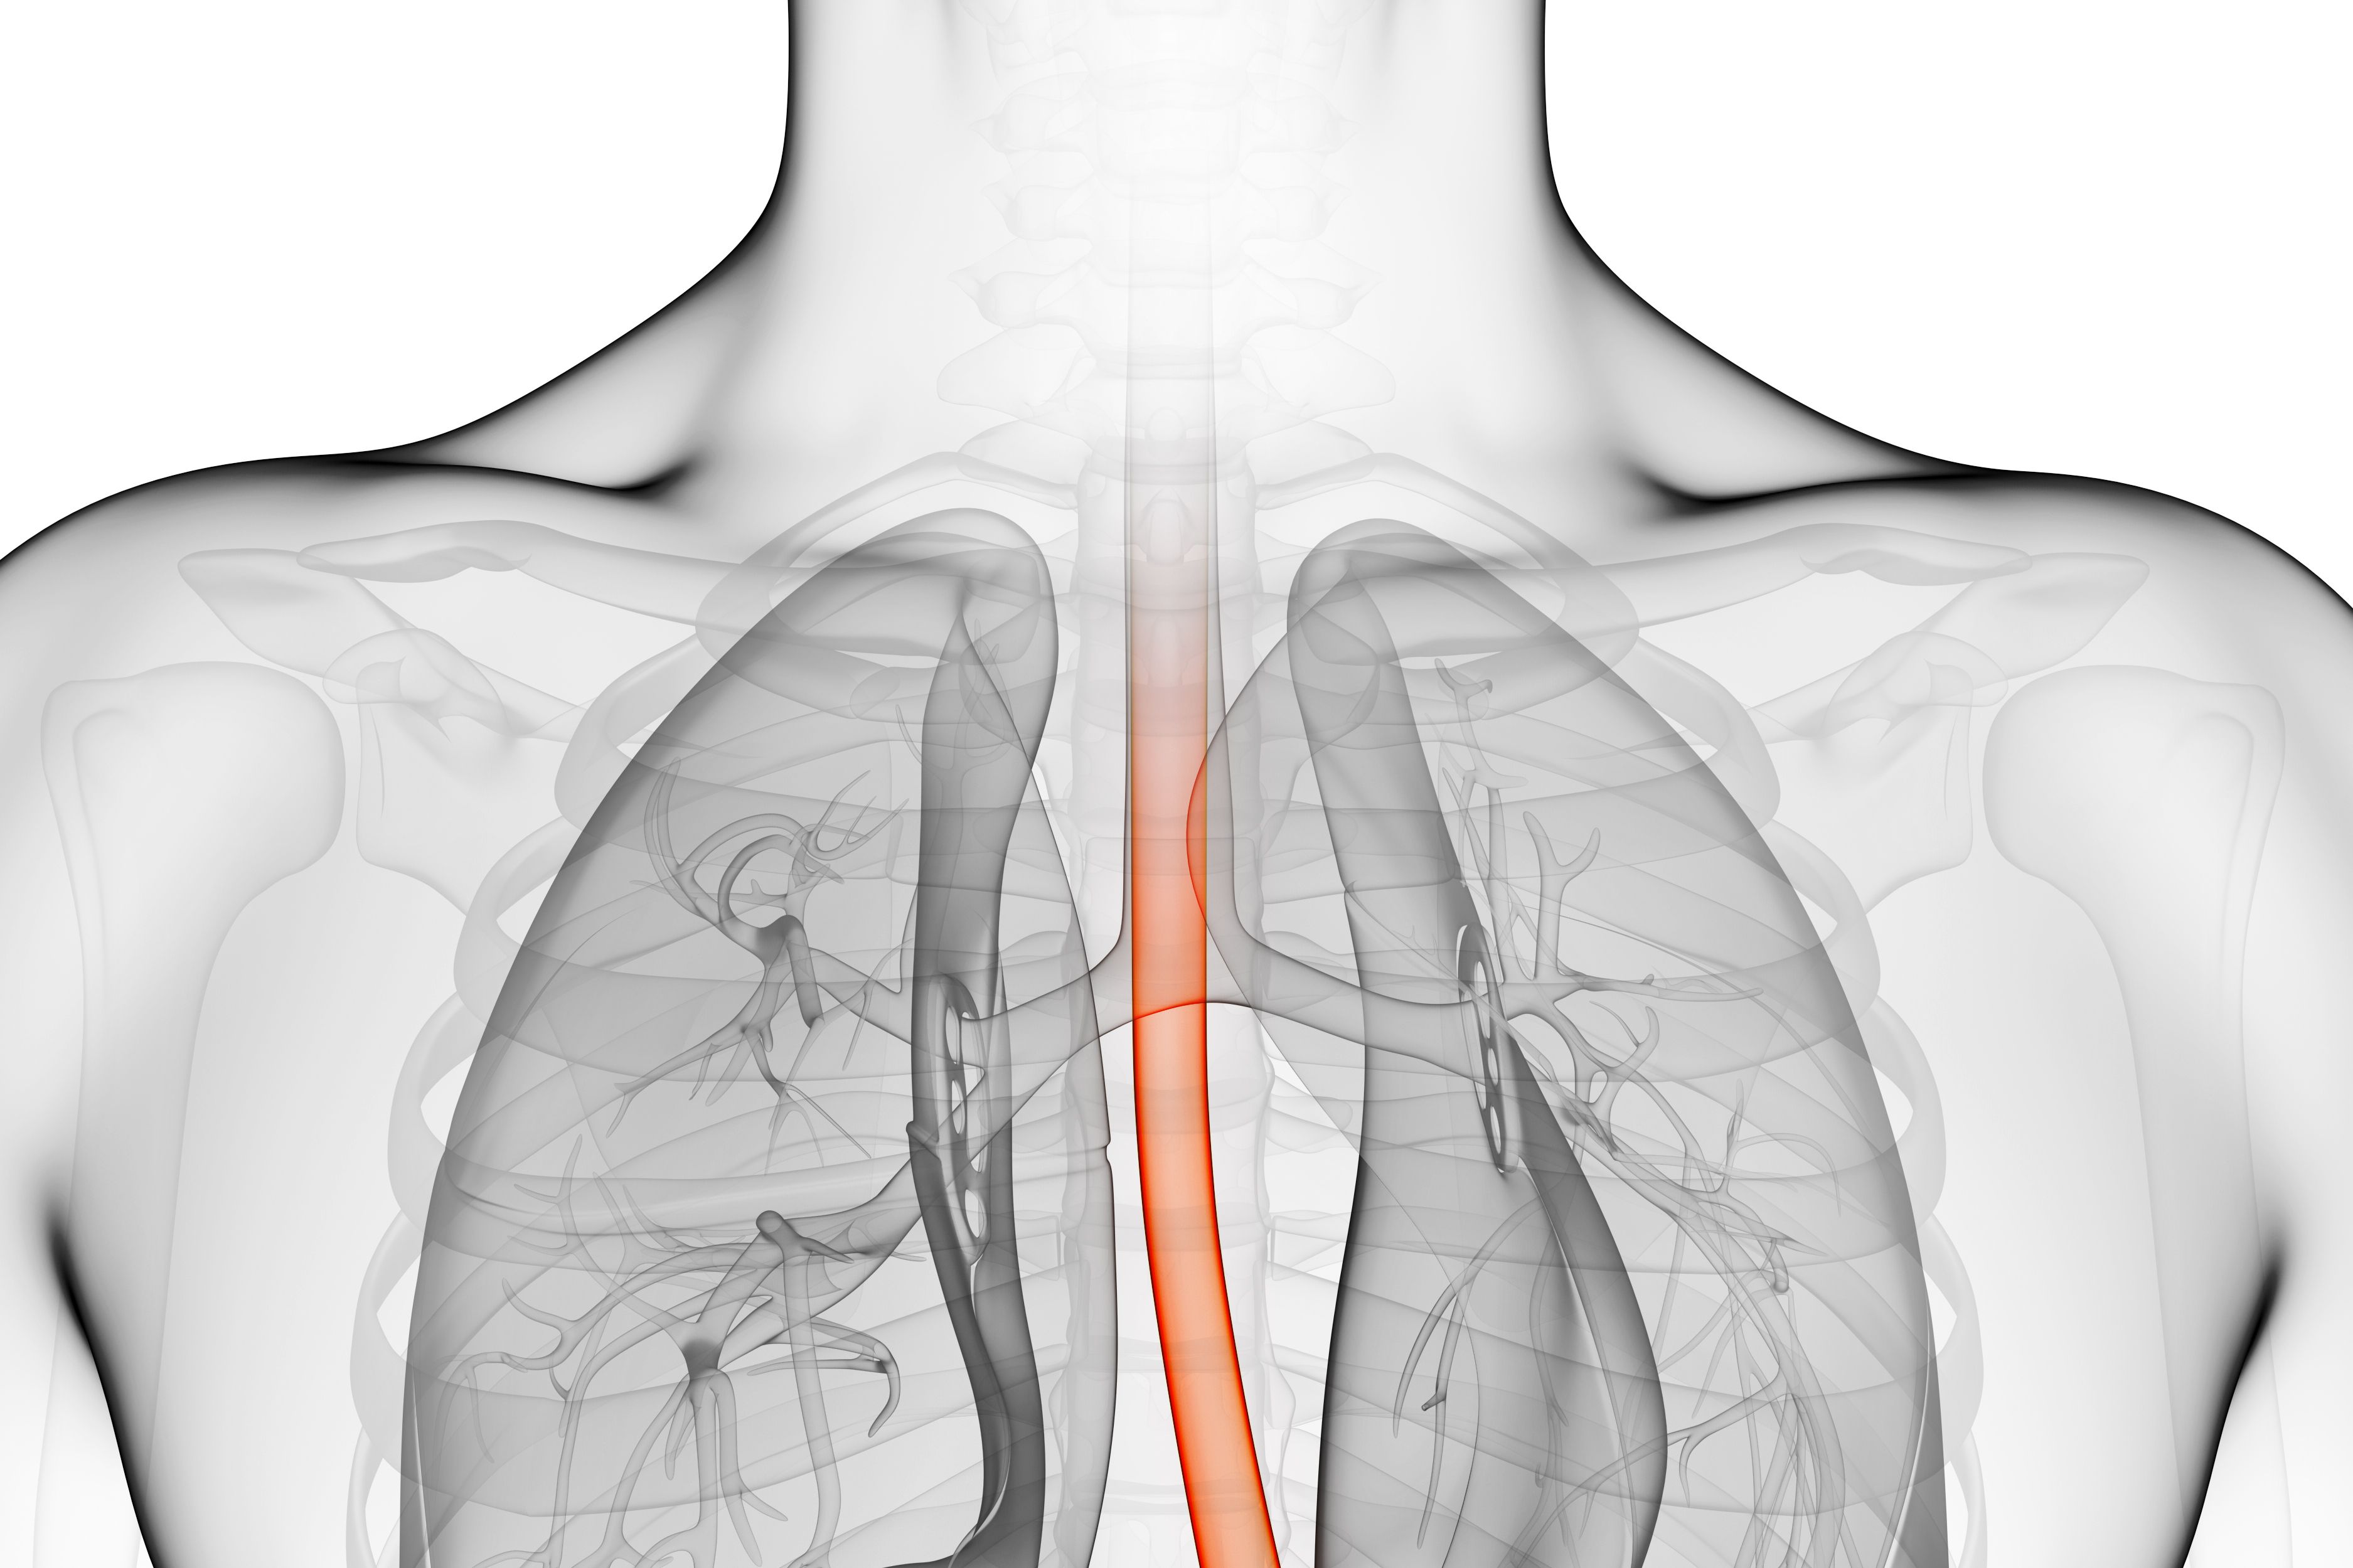

(Vienna, 25 September 2017) Chronic throat irritation, a permanent globus sensation, a sore or dry sensation in the throat are common symptoms, which are often trivialised and wrongly attributed to gastro-oesophageal reflux disease. However, these are also the characteristic symptoms of patients suffering from displaced gastric mucosa in the oesophagus (ectopic mucosa). The recent study conducted by researchers from MedUni Vienna and Vienna General Hospital has now brought a break-through in the treatment of patients with this condition. For the first time in the world, the new radiofrequency ablation technique has been successfully used in severe cases.

The symptoms are caused by a section of misplaced gastric mucosa, which is found in the oesophagus rather than as normal in the stomach during gastroscopy in nearly 10 – 15% of people and this results in chronic damage to the larynx due to the production of acid and mucous. Up until now there has been no safe and effective option for treating pronounced forms of this condition. The first application of radiofrequency ablation brings about a significant improvement in the condition. The study has now been published in the leading journal "Digestive Endoscopy".

"Radiofrequency ablation is a state-of-the-art, minimally invasive technique that has been developed for treating the precancerous stages and early stages of oesophageal cancer, which we offer on an out-patient basis during a gastroscopy," explains Ivan Kristo, lead author of the study and surgeon at the Department of Surgery of MedUni Vienna/Vienna General Hospital (Head: Michael Gnant). He goes on to explain: "This new technique enables us to deliver a controlled charge of energy that destroys unhealthy tissue while causing minimal side-effects. In the patients we have treated so far, the technique produces an improvement that is visible to the doctor and perceptible to the patient."